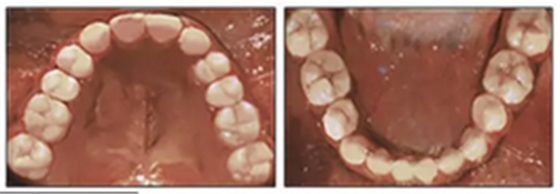

經(jīng)過24個月的保持后,咬合保持得很好(圖11 ; 圖12)。在上牙弓中,應(yīng)用固定舌側(cè)保持器以防止任何復(fù)發(fā)傾向。在下牙弓中,治療后拔除第三磨牙。